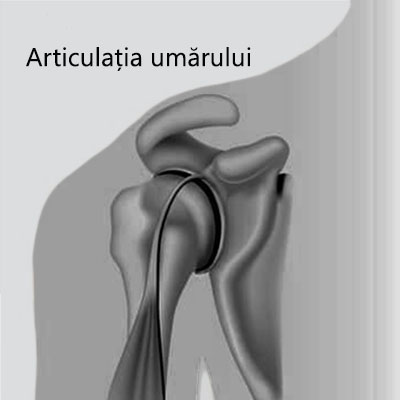

Articulaţia umărului este constituită din trei oase: scapula (omoplatul), humerusul proximal (osul braţului) şi extremitatea externă a claviculei. Capul humeral are forma unei bile şi se articulează cu o scobitură a scapulei numită glenă.

Articulația umărului oferă o arie de miscare foarte mare si o flexibilitate mult mai crescuta decat alte articulații din corp, fiind in consecință si articulația cea mai predispusă la luxații si subluxații.

Traumatismele recurente, luxațiile scapulo-humerale sau laxitatea congenitală a părților moi poate duce la o afecțiune cronică numită instabilitate articulară. Umărul poate fi afectat de o instabilitate anterioară, posterioară şi inferioară.